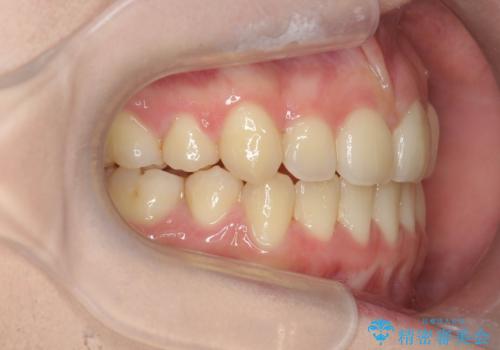

歯並びのせいで歯ブラシがしづらい マルチブラケットを用いた抜歯矯正

- 歯並びのがたつきにより歯ブラシがしづらく、今後虫歯になってしまう不安から、矯正治療を希望されて来院されました。

歯を並べるにはスペースが不足しているため、小臼歯の抜歯を4本行うマルチブラケット矯正による治療を計画します。

治療後は非常に歯ブラシがしやすくなったと、治療結果に満足いただくことができました。